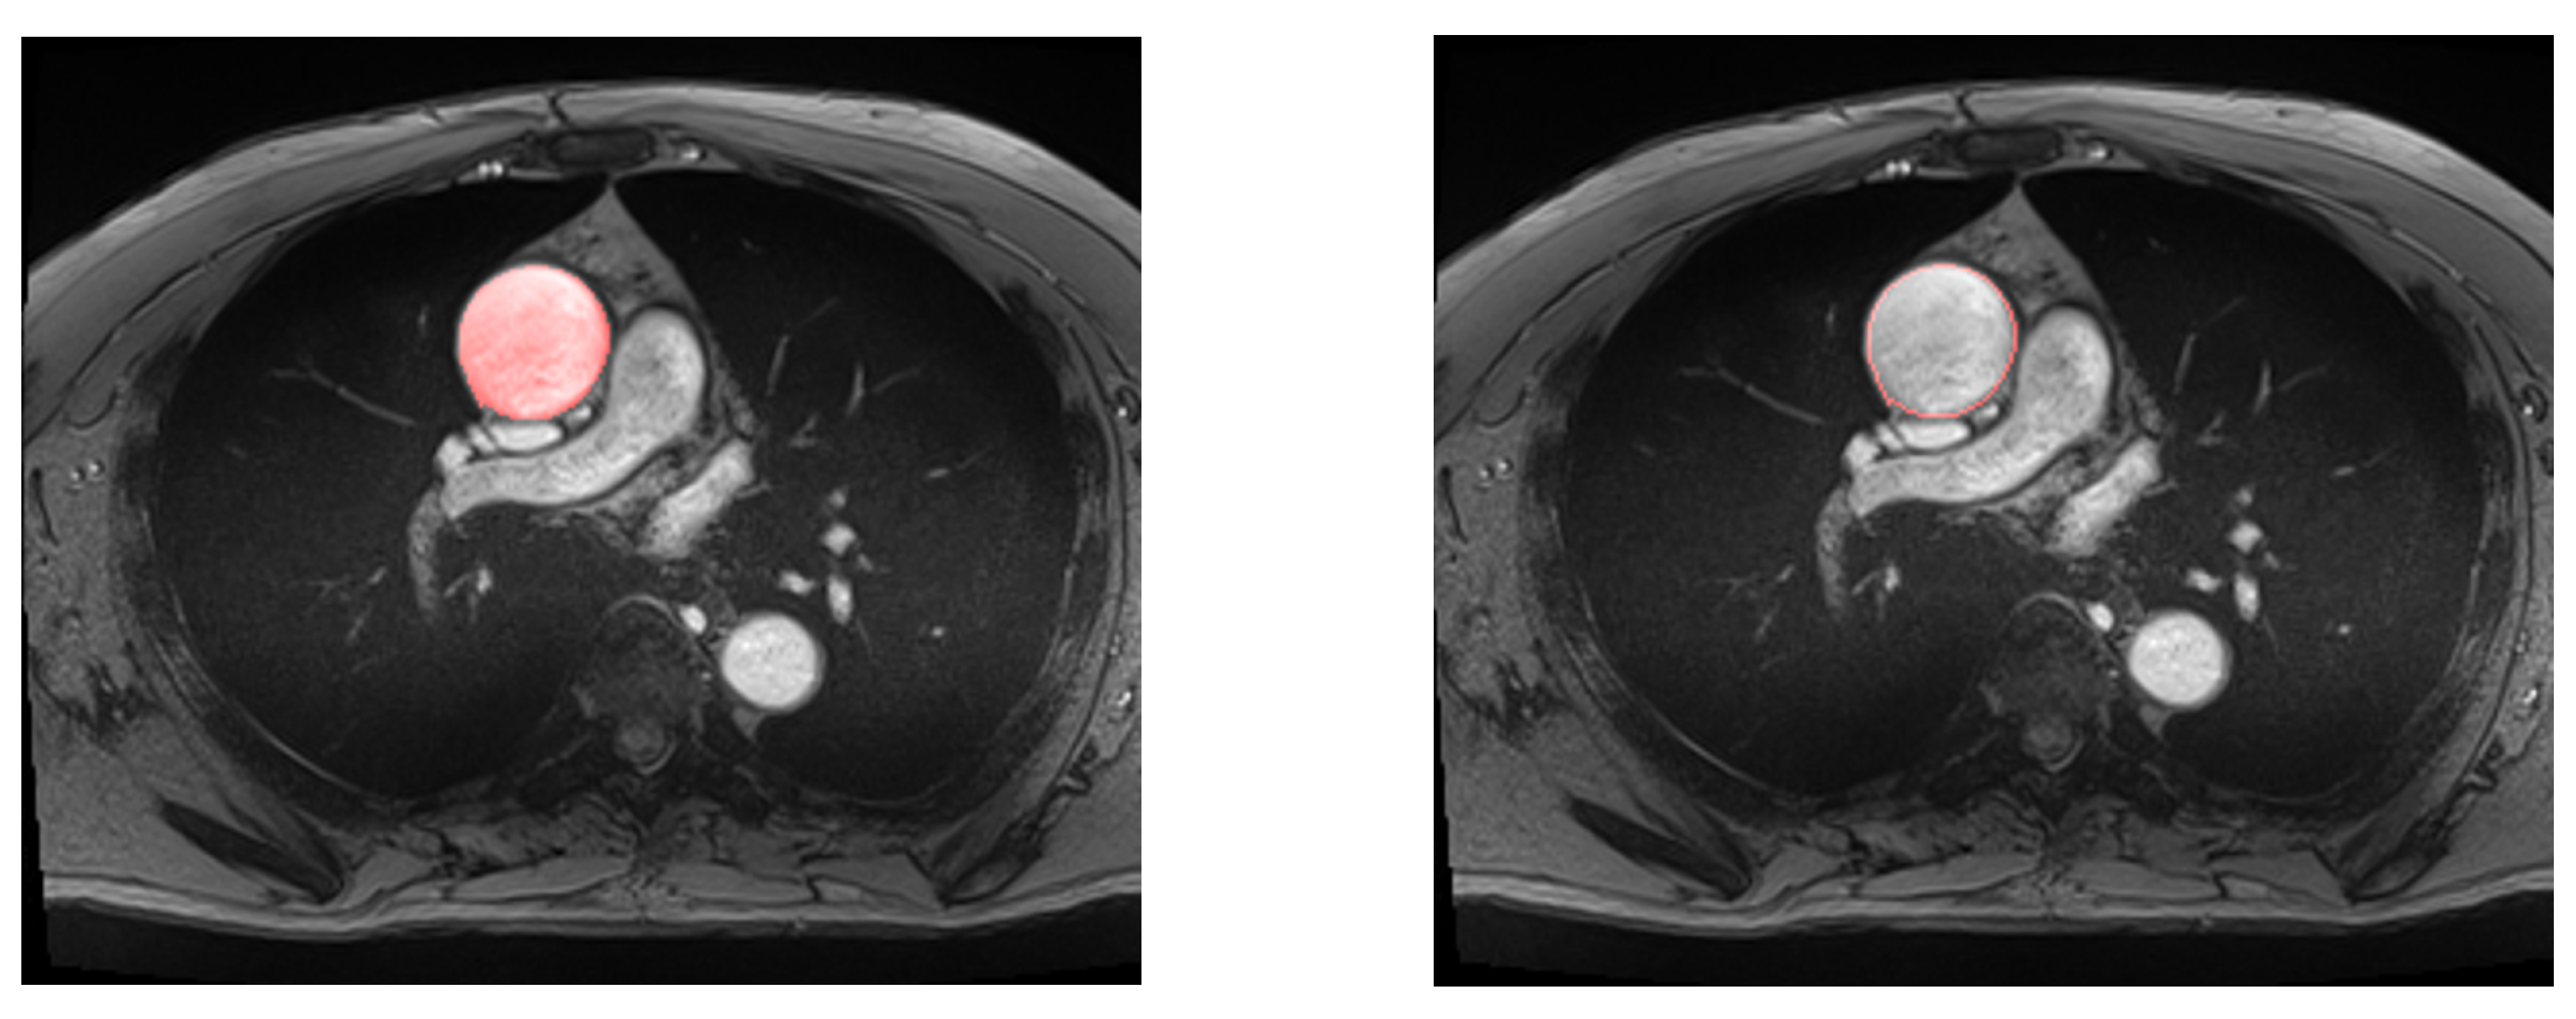

Table 2 presents the results of all of the considered models. The performance of the simple U-Net architecture is displayed in Figure 7.

Figure 7.

Example of automatic segmentation of the ascending aorta with our U-Net architecture. On the left, all the aortic surface is colored, in contrast to the right, where only the aortic wall is displayed.

Considering that residual U-Net and simple U-Net had the highest performance, the simple U-Net was selected for the next phases as it has less complex architecture and provides a lower Hausdorff distance.